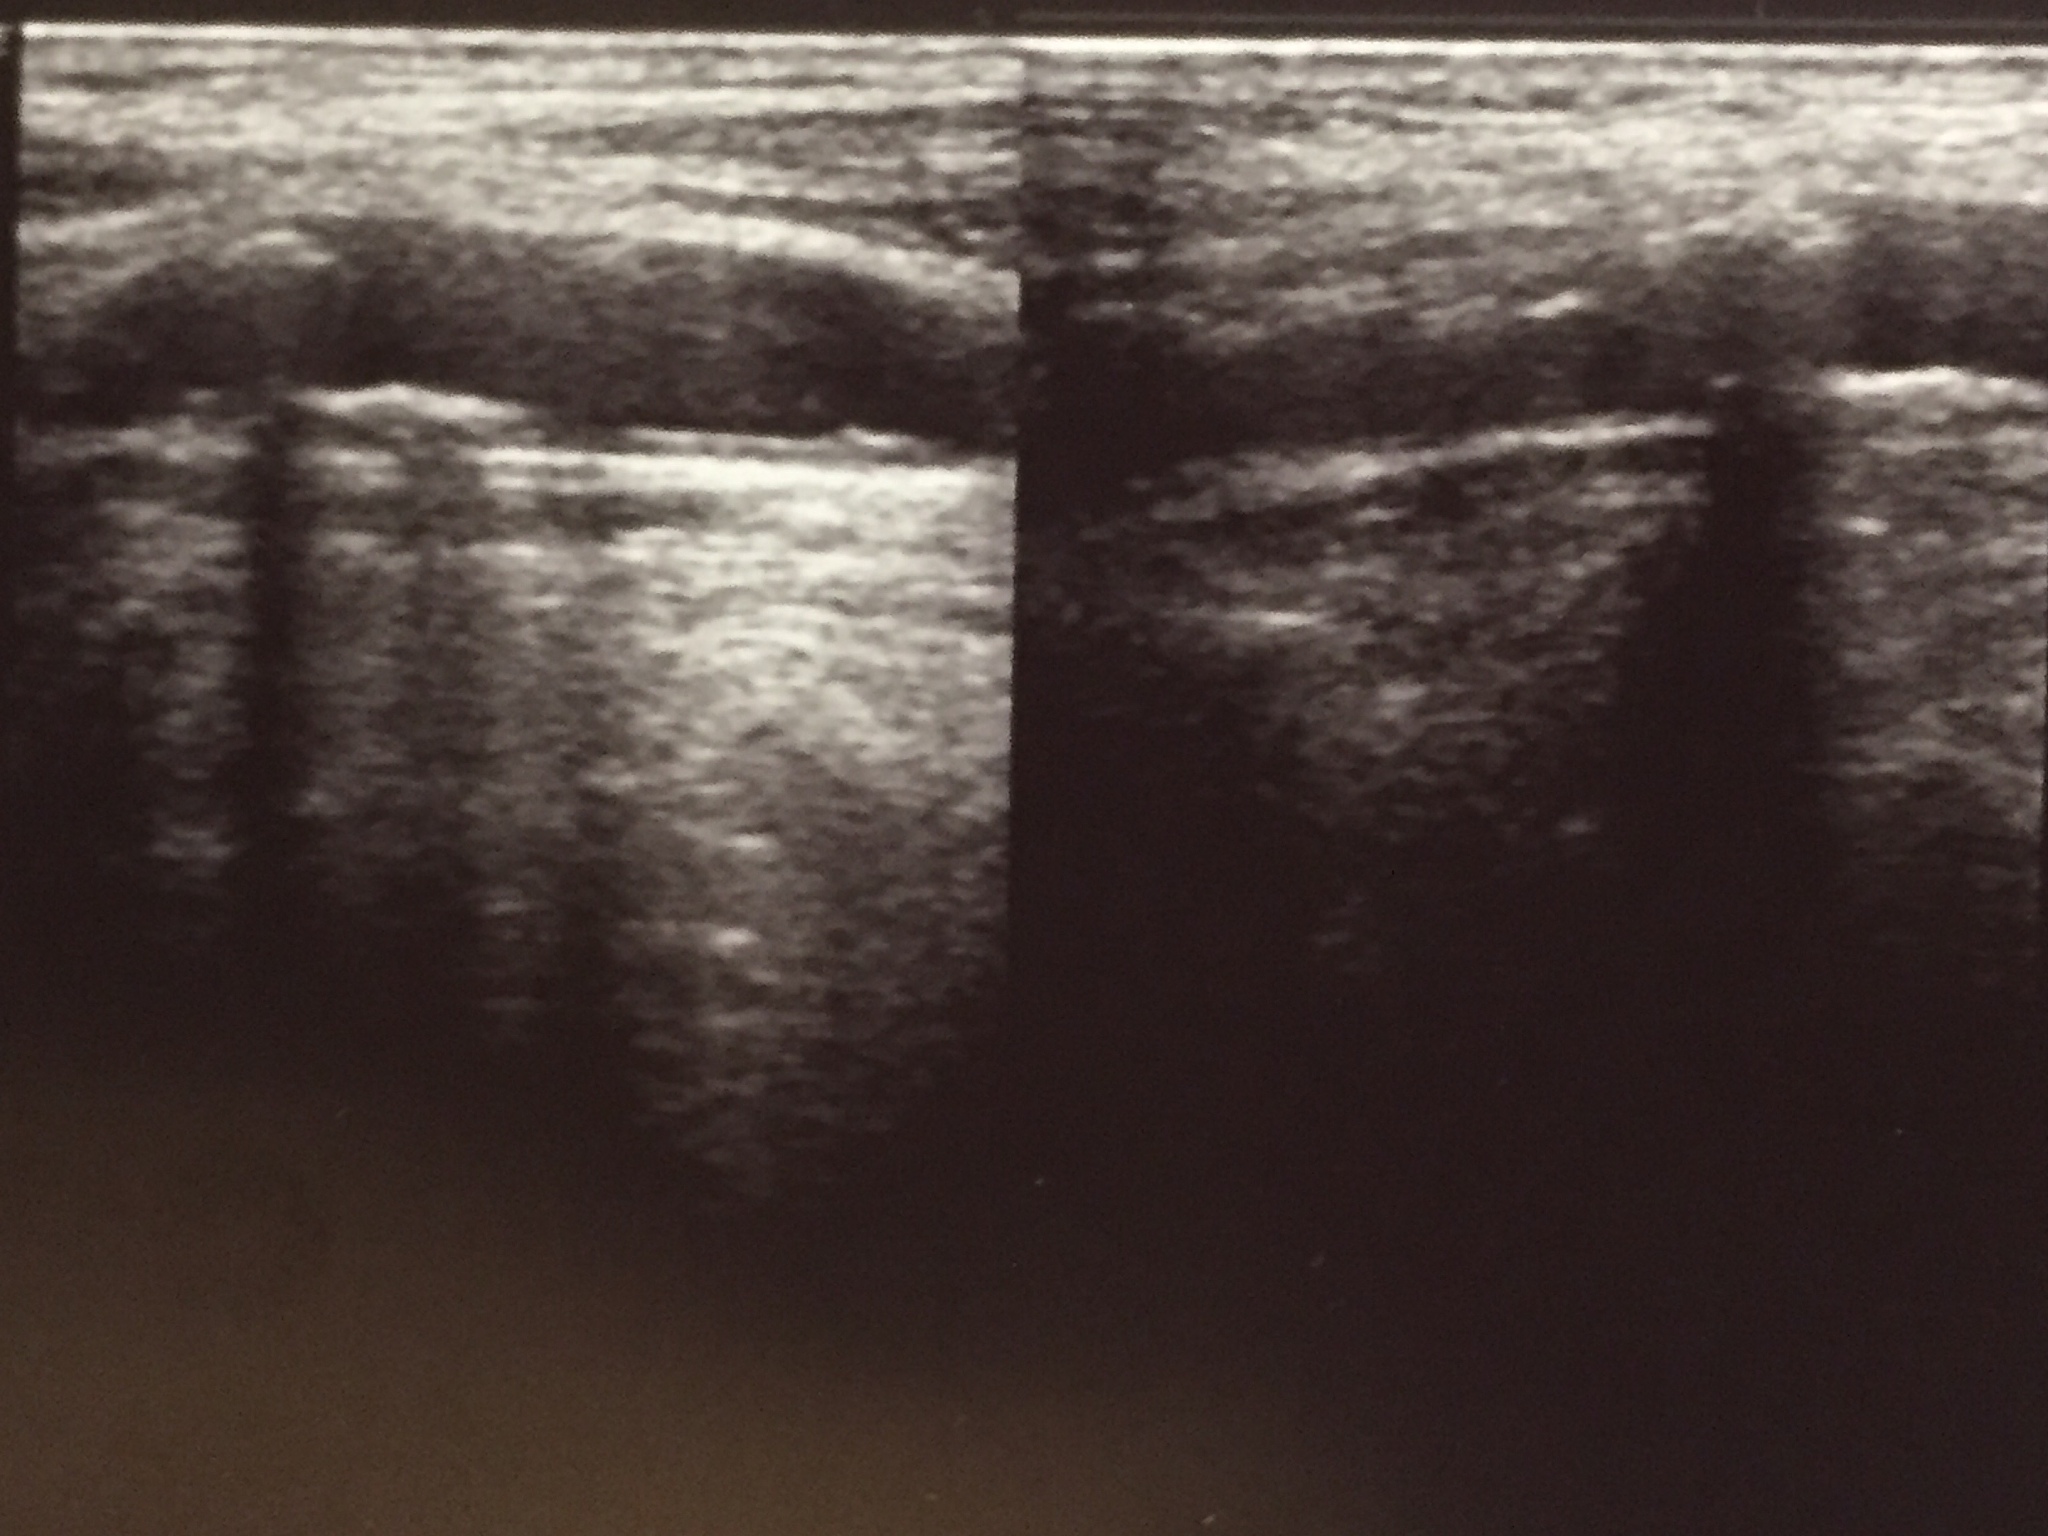

越来越多的研究表明,超声造影可以通过检测斑块内新生血管来评估斑块的易损性。研究认为颈动脉斑块增强程度与斑块内新生血管密度及斑块回声相关,与颈动脉狭窄程度无关。